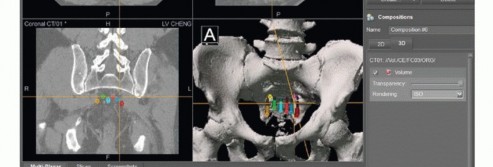

التخطيط قبل الجراحة

يُعد التخطيط الدقيق قبل الجراحة أمرًا حاسمًا لنجاح العملية. يقوم الأستاذ الدكتور محمد هطيف بمراجعة شاملة لجميع صور ما قبل الجراحة (الأشعة السينية، التصوير المقطعي، الرنين المغناطيسي، تصوير الأوعية الدموية) لتحديد خطة جراحية واضحة وتقييم الدواعي والمخاطر.

- تحديد مدى الاستئصال: يجب تحديد المدى العلوي للاستئصال بدقة لتحقيق استئصال فعال. الهدف هو إنقاذ أكبر عدد ممكن من الأعصاب العجزية مع الحفاظ على هوامش جيدة.

- التقنيات المتقدمة: في الحالات التي يتم فيها التخطيط لجراحة بمساعدة الملاحة الحاسوبية، يتم دمج صور التصوير المقطعي والرنين المغناطيسي وتصميم الجراحة بالتفصيل.